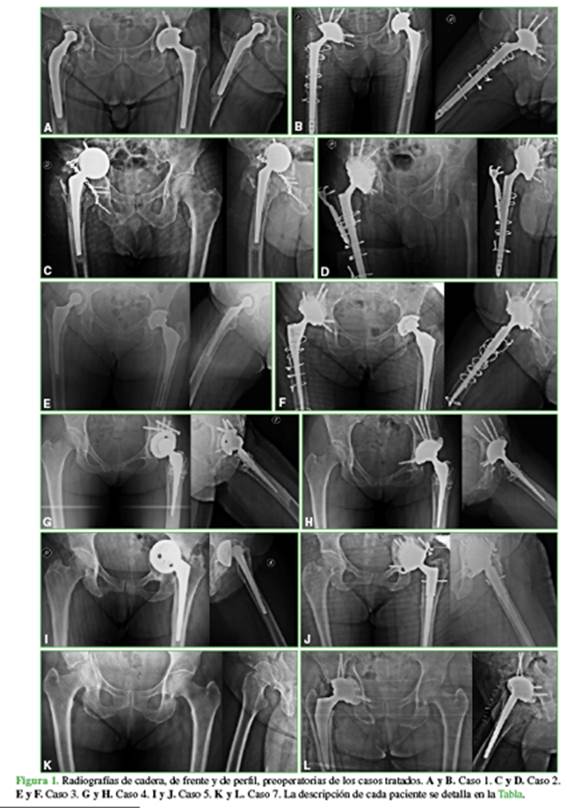

De acuerdo con el protocolo, se toman radiografías de frente panorámico de ambas caderas, de entrada y salida pélvica, alar y obturatriz (Figura 1A, C, E, G, H, I, K).

Los siguientes controles se realizaron con radiografías a las 6 semanas, los 2 y 3 meses, y se indicó el retiro del andador y carga con bastón canadiense. Al sexto mes, se retiró la asistencia para carga de peso y se establecieron controles cada seis meses (Figura 1B, D, F, H, J, L). Hasta el momento, no se han registrado complicaciones posoperatorias.